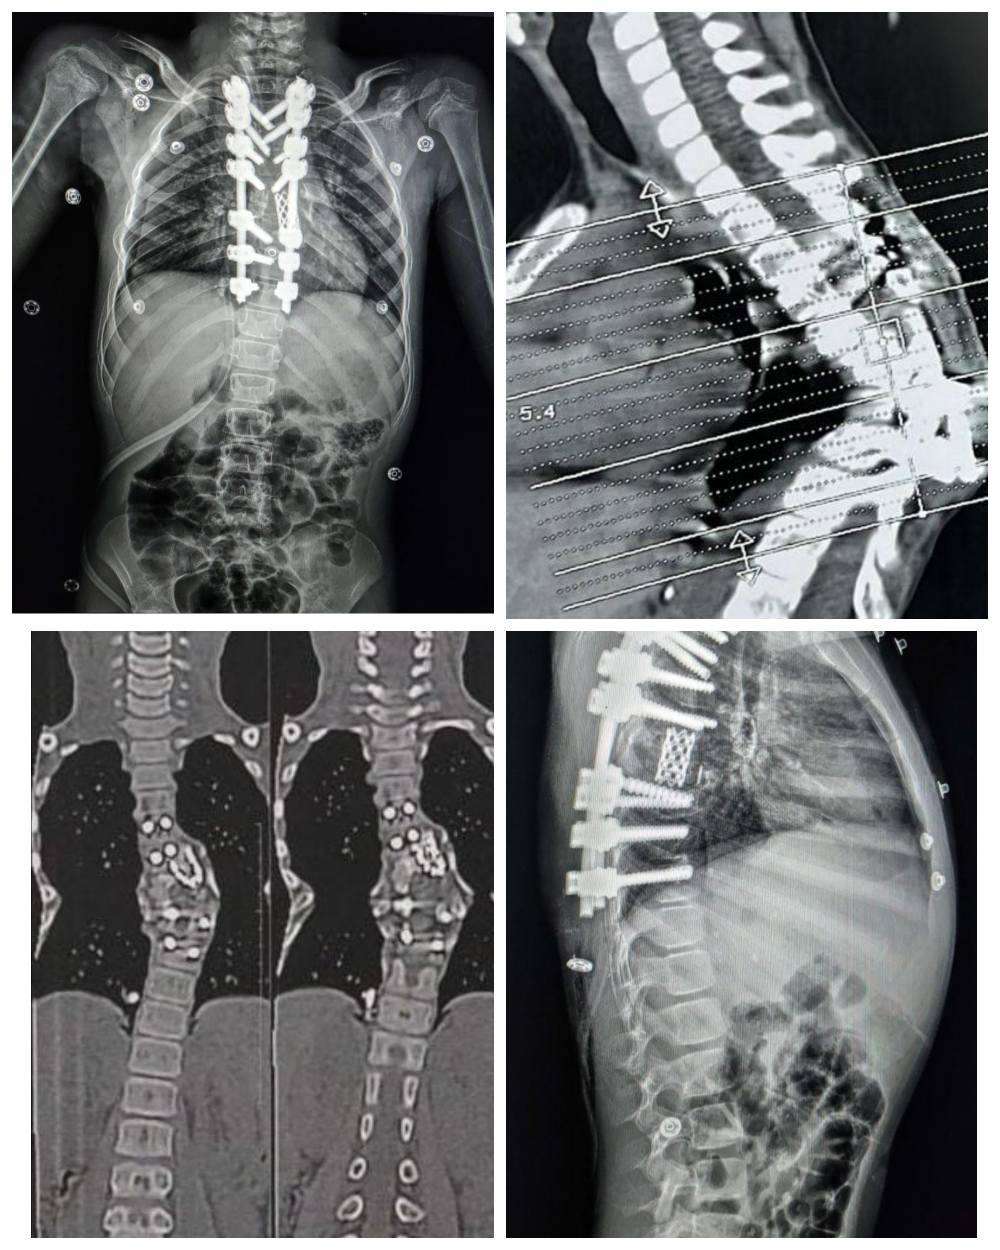

كان مستشفى الإصابات قد استقبل طفلة تعاني من تحدب شديد وصل إلى 85 درجة نتيجة لدرن فقري سابق، وهو ما كان يهدد حركتها ونموها بشكل طبيعي.

كان التشوه ناتجا عن درن في العمود الفقري، وقد زاد الأمر تعقيدا بسبب وجود جراحة سابقة، أجريت لها بإحدى المستشفيات، لتثبيت الفقرات بواسطة مسامير وأعمده وقفص معدني، وإلتئام كامل للفقرات في وضع معيب، مما أدى إلى حدوث تحدب واعوجاج حاد في الفقرات الظهرية، ليقرر الفريق الطبي الذي ضم كل من، الدكتور عمرو حاتم، مدرس جراحة العظام والعمود الفقري، والطبيب محمد خالد، مدرس مساعد بالقسم، والدكتور شادي نادي، أخصائي جراحة العظام والعمود الفقري، والطبيب خالد محسن، مدرس مساعد بالقسم، والطبيب مينا مفدي، نائب بالقسم، والطبيب محمد جمال نائب بالقسم، ويعاونهم فريق من قسم التخدير جاء تحت إشراف الأستاذة الدكتورة هالة سعد رئيس القسم، وضم، الدكتور محمود فيصل، مدرس التخدير والعناية، والطبيب محمد رفعت، مدرس مساعد بالقسم، والطبيب لؤي جمال، مدرس مساعد بالقسم، والطبيبة سارة جمال، نائب بالقسم، ومن هيئة التمريض، الأستاذة هاجر محي، والأستاذ محمد بدر، والأستاذ عمر مصطفى، بإجراء جراحة دقيقة للغاية بسبب صغر سن الطفلة وشدة التشوه، لاستعدال التشوه مع تثبيت الفقرات بدقة، وقد تطلبت الجراحة تقييمات وقياسات معقدة لضمان تحقيق تصحيح كبير دون إلحاق ضرر بالأعصاب الطرفية.

كما قام الفريق الطبي باستخدام جهاز مراقبة الأعصاب، وهو تقنية حديثة متقدمة لجراحات العمود الفقري، وتعد الأولى من نوعها بصعيد مصر، لإجراء شق عظمي لفقرتين من الفقرات الظهرية، واستعدال وتثبيت الفقرات بمسامير فقرات وأعمده وقفص كربوني، بالإضافة إلى ذلك، استخدم فريق التخدير تقنيات حديثة وغير تقليدية سمحت بالمراقبة الفسيولوجية اللحظية للأعصاب والعضلات طوال فترة العملية.

وبفضل هذه الجهود من الفريق الطبي، تم تصحيح التشوه بنجاح، وخرجت الطفلة من العملية في حالة مستقرة، وعادت إليها الحركة بصورة طبيعية.